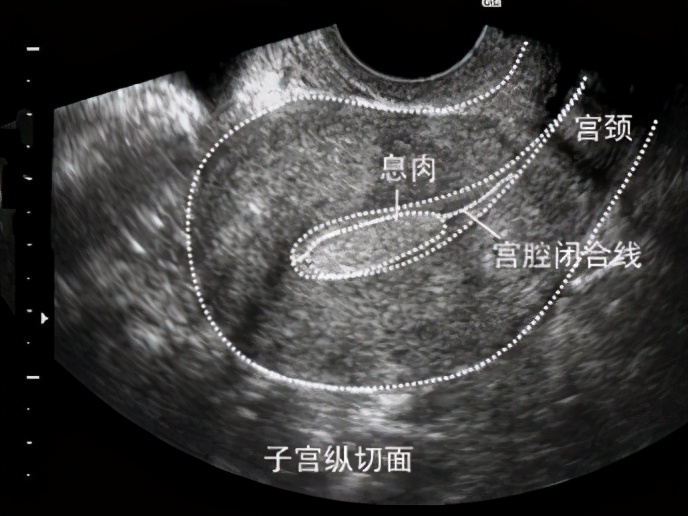

子宫内膜息肉是子宫局部间质过度生长被覆良性腺体上皮。子宫内膜息肉的大小不一,直径从数毫米到数厘米,可以是单个或多个,可以有蒂也可无蒂。如果说子宫内膜是土壤,那子宫内膜息肉就是杂草。

很多时候,患者在做完超声,才发现“子宫内膜息肉”,但最终是需要依靠切除息肉组织后的病理检查才能确定。